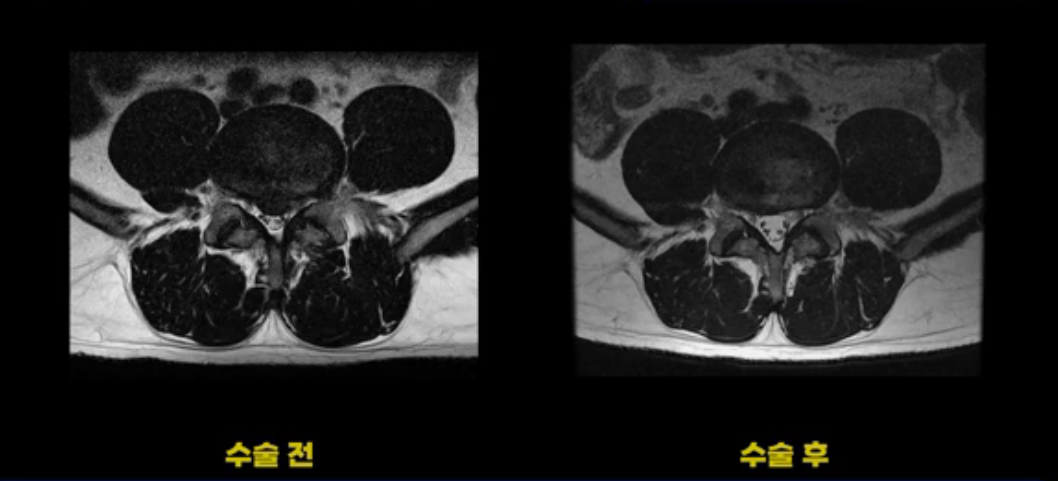

이 환자분은 디스크 파열 수술 후 3개월 정도 괜찮았다가 그 이후 점점 다리 저림과 통증이 다시 시작되어 수술 후 1년 정도부터는 거의 수술 전에 아팠던 정도까지 증상이 악화됩니다. 그런데 이분 수술 후 MRI를 보면 수술이 잘 돼서 깨끗합니다.

보시다시피 수술 전의 MRI와 비교해 보면 밀려 나온 디스크 수핵이 거의 대부분 깨끗이 제거되었습니다.